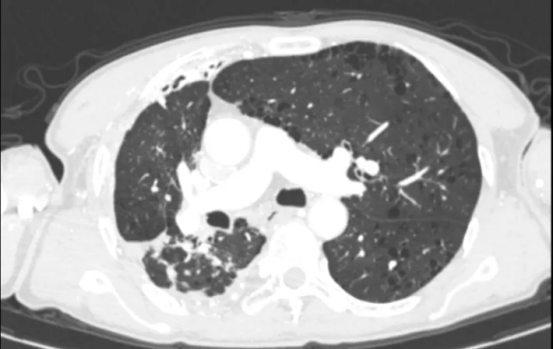

术前影像(左右滑动查看更多)

该患者为61岁男性,肺部病情错综复杂。4年前确诊肺结核后因治疗不规范,发展为“利福平耐药”结核,病情持续恶化。2年来反复咯血,虽经3次支气管动脉栓塞术暂时控制,但病灶顽固,收治入院时已形成多重诊断:毁损肺(右上)、右肺下叶鳞癌(背段)、肺曲霉菌病、陈旧性肺结核。其右肺上叶完全丧失功能,并与胸壁形成致密粘连,医学上称为“毁损肺”——胸外科领域公认的极高难度手术。